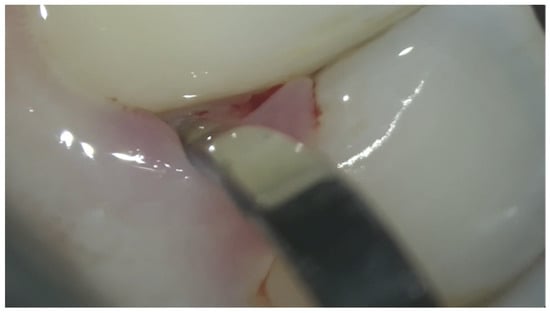

6.1. Manual Instrumentation